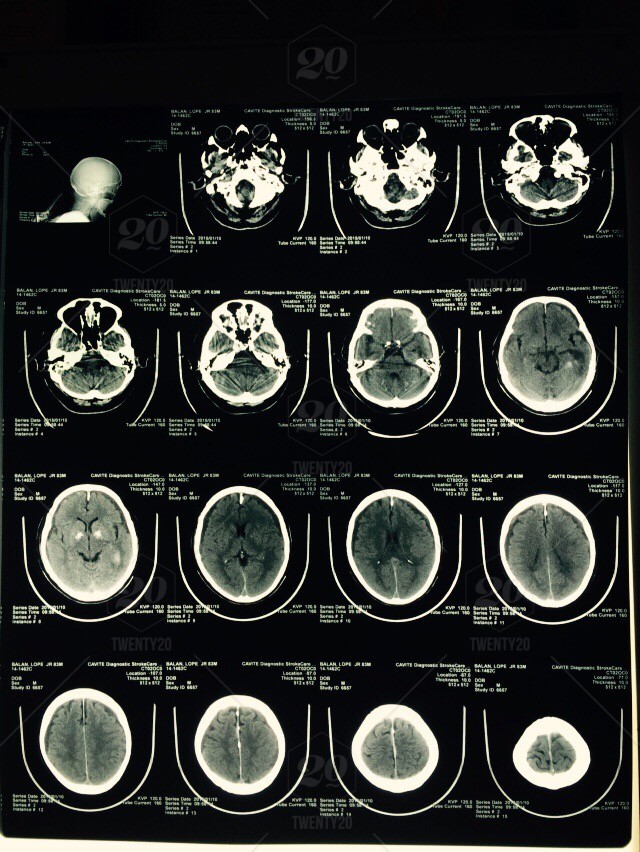

Imaging technology has become more useful for preventing surgery and aiding in its success. Technologies such as CT (computed tomography) scans have expanded the breadth of diagnostic methodologies available to physicians. Dr. Myriam Martinez in Boston, Massachusetts, sought to pinpoint the usefulness of CT technology in allowing for necrotizing soft infections (NSTI) diagnoses. The researchers found that NSTIs could be examined effectively with computed tomography (CT) scans of the contrast-enhanced category.

The researchers analyzed medical record data relating to 184 patients admitted for a suspected NSTI. The patients underwent a CT scan with intravenous contrast, along with gas in soft tissue, multiple fluid collections, tissue enhancement, and connective tissue inflammation as NSTI markers sought out from the scan results. STATA software was used to perform t-test analyses.

Positive CT scans occurred in 9% of the selected patients, and following surgery, 76% were found to have a NSTI. In patients with negative CT scans, 23% underwent surgery because it was thought that they had NSTIs, but these patients had non-necrotizing infections. 77% of patients were treated without any operations. Two variables that were significantly different between NSTI diagnosed and non-NSTI diagnosed patients were white blood cell counts and hemoglobin levels.

Although the sample size was small, the researchers suggested that CT imaging technology was an effective supplement to surgery-related decisions concerning suspected NSTIs. They suggested that NSTI symptoms were often missed or indistinguishable from other diseases, leading to high mortality rates that could be reduced through CT technology. In the future, computed tomography could be refined into a non-invasive way of detecting NSTIs, with surgeons being trained to identify them.